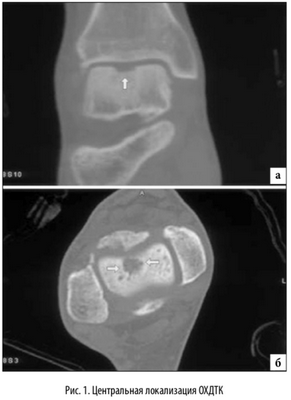

Наиболее распространенной локализацией остеохондральных повреждений таранной кости является переднелатеральной и заднемедиальной край суставной поверхности таранной кости. Исследование, основанное на изучении МРТ данных, проведенное Hembree с соавт. [14], определило, что большинство выявляемых локализаций остеохондральных повреждений таранной кости располагались медиально и центрально [15]. Независимо от этого, латеральная локализация данных повреждений связана с травмой от 93% до 98% случаев. Однако, было отмечено, что повреждения латеральной локализации в основном имеют меньшую и правильную овальную форму и возникают при эверсионных движениях в максимальном подошвенном сгибании стопы [16]. Медиальные повреждения связаны с острой травмой реже, от 61% до 70% [5]. Считается, что медиальные поврежде ния, вызваны повторяющейся микротравмой, вызванной соударением медиального края суставной поверхности таранной кости о суставную поверхность большеберцовой кости в момент максимальной супинации стопы. Медиально локализующиеся повреждения глубже, кратерообразной формы, и образуются при максимальном подошвенном сгибании стопы [16]. Остеохондральные повреждения с центральной локализацией имеют мультифакторный механизм образования и наиболее сложны в плане хирургического лечения (рис. 1).